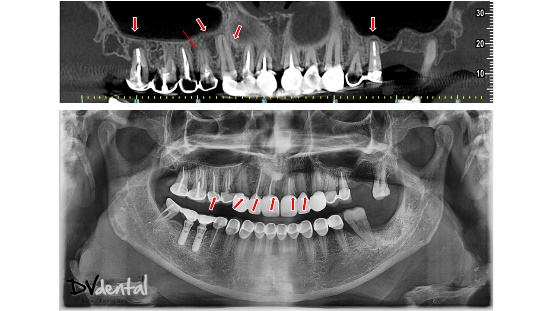

A 52-year-old female patient presented with significant decay, cysts, and fractures in several upper teeth, as revealed by X-ray examination. All available treatment options were thoroughly discussed with the patient, who chose to proceed with implant therapy for a more favorable long-term prognosis.

Fig 2(Left): The X-ray examination and symptom diagnosis